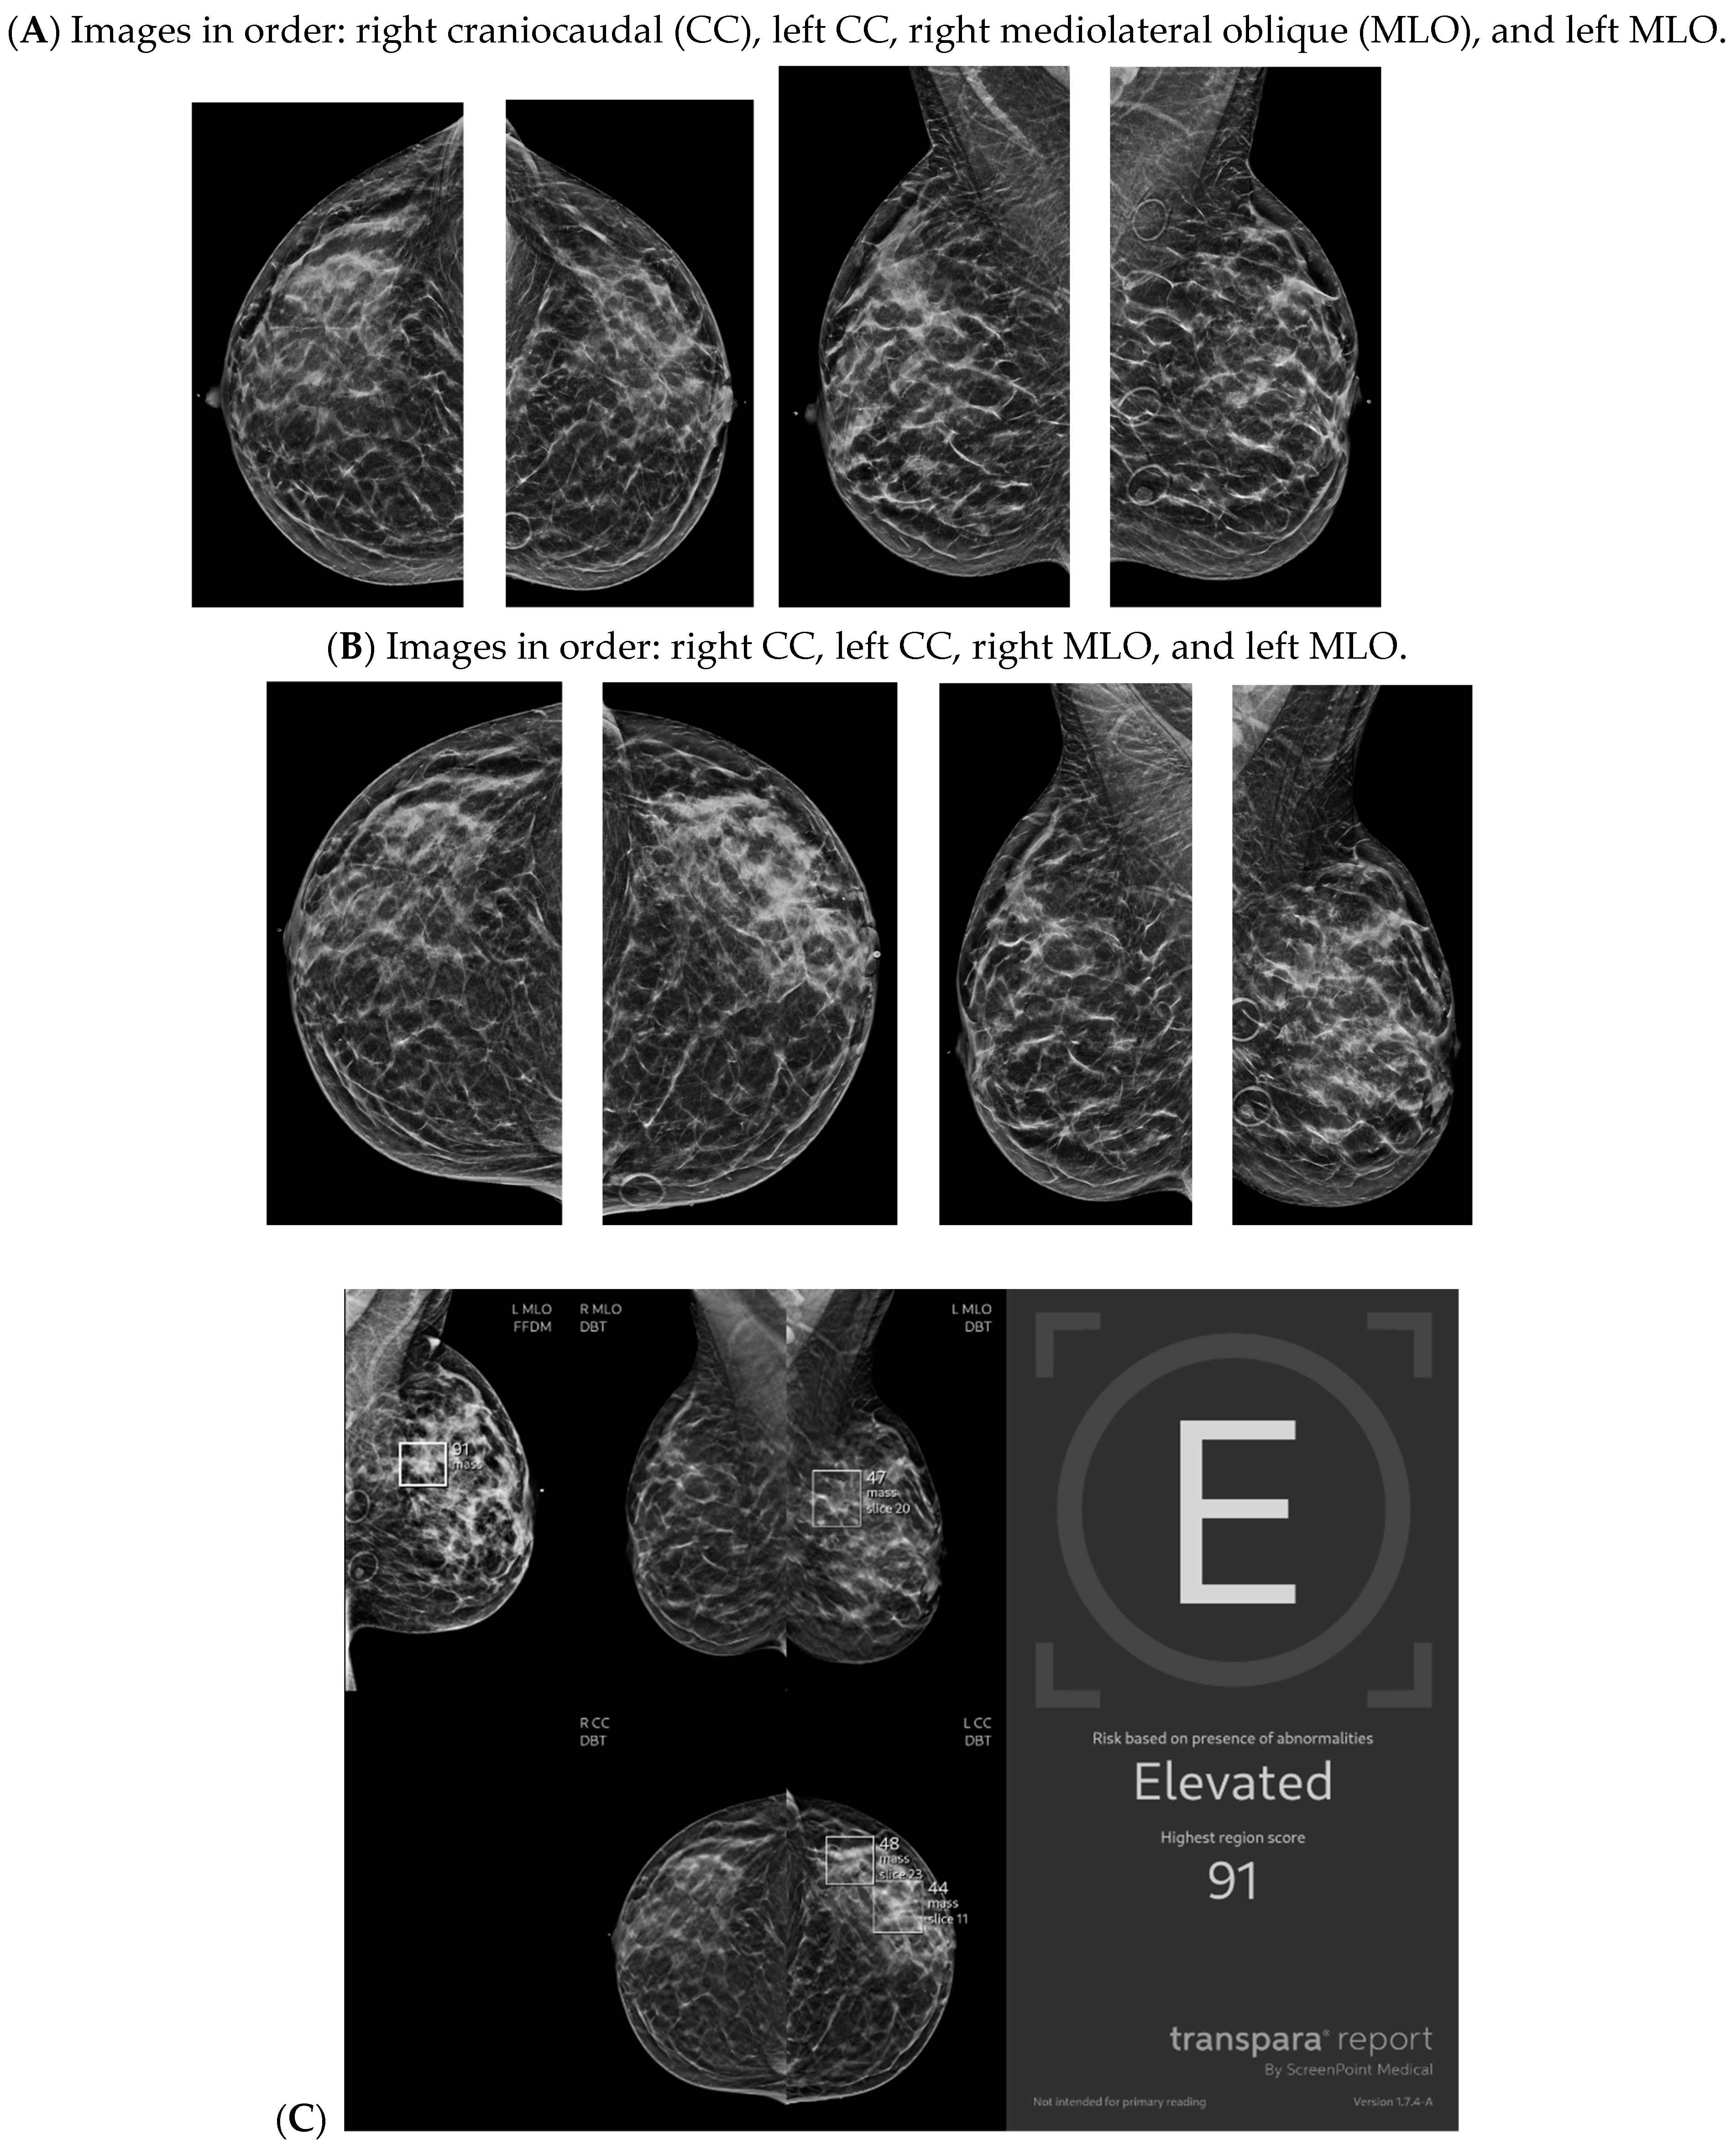

With the widespread implementation of DBT, which increases mammographic cancer detection sensitivity, there are larger volumes of images. This may ultimately increase the risk of reduced accuracy, perhaps due to reader fatigue and increased reading time [24]. There are numerous tomosynthesis AI products available, and at our institution we have implemented the use of Transpara, which is a deep learning-based AI system that uses deep CNN to help improve early-stage cancer detection and sensitivity (at similar specificity), while reducing reading time [24,25]. We view tomosynthesis AI as a valued asset to our clinical practice, as the software highlights potential areas of concern that require additional attention (Figure 1 and Figure 2). However, some areas flagged as concerning are often classically considered benign, such as stable post-lumpectomy sites, stable asymmetries and calcifications, or previously biopsied benign findings. That being said, tomosynthesis AI has been found to have a synergistic effect on cancer detection rate (CDR) when utilized by the radiologist. A study found that radiologist-only CDR was 67.3% and AI-only CDR was 72.7%, but when the radiologist and AI software were used together, the CDR increased to 83.6% [17,25,26]. Lunit INSIGHT MMG, Seoul, South Korea was the diagnostic support software used in this particular study [26].

Figure 1.

Developing asymmetry detected by artificial intelligence (AI): Between the baseline screening mammogram (A) and the follow-up screening mammogram 17 months later (B), there has been a very subtle development of left breast asymmetry that is difficult to perceive with the naked eye. However, the AI program Transpara highlighted potential regions of interest (C) for the radiologist to query for additional mammographic and sonographic imaging. On further diagnostic imaging, the subtle asymmetry corresponds to a hypoechoic mass at left 4:00, 3 cm FN (D) with hypervascularity (E). AI program Koios correctly recognized the mass as “Probably Malignant”, and this area returned as a biopsy-proven invasive malignancy with lymphangitic spread (F). Images obtained from the Icahn School of Medicine at Mount Sinai.

Figure 2.

New architectural distortion detected by artificial intelligence (AI): A patient in her 50s’ screening mammogram revealed a new area of architectural distortion (circle) in the inner central region of the left breast (A). The AI program Transpara highlighted potential regions of interest, including this suspicious area of architectural distortion on the left breast on the corresponding left CC view; however, AI also highlighted benign areas that were arbitrated out by the radiologist (B). There was no sonographic correlate, so a stereotactic biopsy of this area of architectural distortion was then biopsied under guidance. Pathology yielded invasive lobular carcinoma. Images obtained from the Icahn School of Medicine at Mount Sinai.